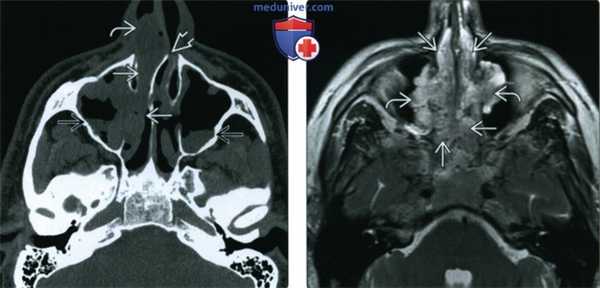

(Слева) При аксиальной КТ без КУ визуализируется большой полип, заполняющий полость носа справа, и выбухающий из правой ноздри. Обратите внимание на доброкачественное ремоделирование костей и смещение влево костной носовой перегородки. Уровни «жидкость-газ» с пузырьками газа в верхнечелюстных пазухах неспецифичны и могут быть обусловлены воспалительным компонентом при остром синусите.

(Справа) При аксиальной MPT Т2ВИ у пациента с тяжелым полипозом визуализируются множественные гиперинтенсивные полипы, заполняющие полость носа и внутренние отделы верхнечелюстных пазух.

(Слева) При аксиальной МРТ Т2ВИ FS визуализируются гипоинтенсивные полипы, заполняющие решетчатые и основные пазухи и приводящие к их вздутию. На Т2 ВИ гипоинтенсивные полипы имитируют газ в пазухах.

(Справа) При сагиттальной МРТ Т1ВИ С+ у этого же пациента в полости носа визуализируются множественные полипы, накапливающие контраст. Полипы в основной пазухе характеризуются сигналом смешанной интенсивности. Обратите внимание на выраженное истончение кортикального слоя ската.